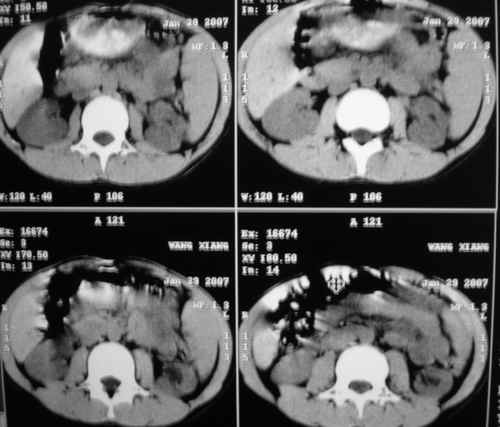

m 15y 外院b超发现左肾包块,遂来ct检查。

左肾外形明显小于右肾,左肾中上极后侧可见一等密度影,与肾分解不清,肾盂肾盏无扩张,先考虑:左肾发育不良,建议强化除外占位

左肾外形明显小于右肾,左肾中上极后侧可见一等低密度影,与肾分解不清,肾盂肾盏无扩张,先考虑:左肾发育不良,平滑肌脂肪瘤待排除。